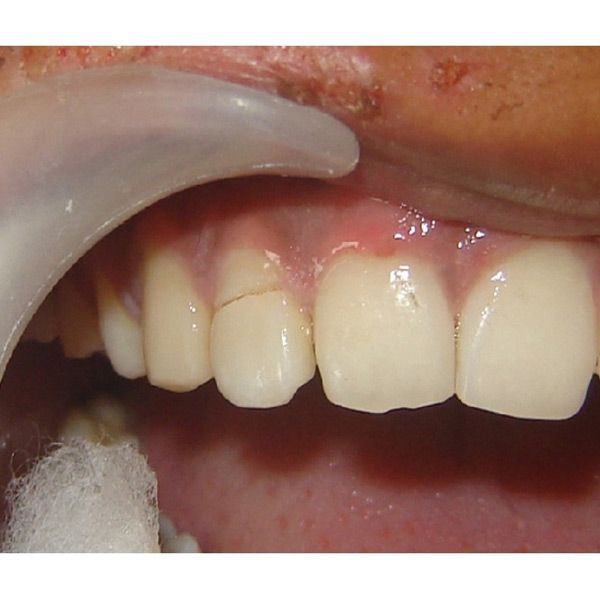

جراحی لثه(افزایش طول تاج)

ترمیم کامپوزیت